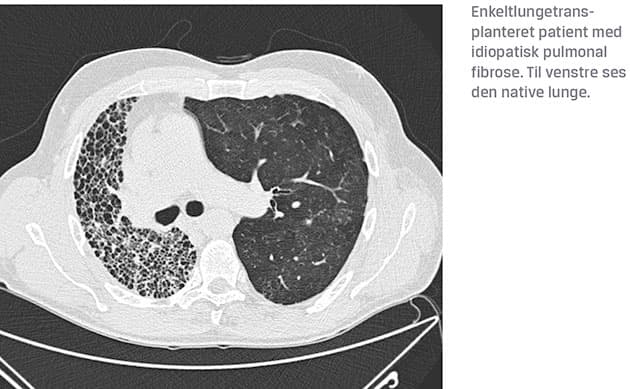

Samlet har man i det danske LTx-program gennem årene behandlet flest patienter med kronisk obstruktiv lungesygdom og emfysem (Figur 1). I de senere år er andelen af patienter med fibrotisk interstitiel lungesygdom steget [3].